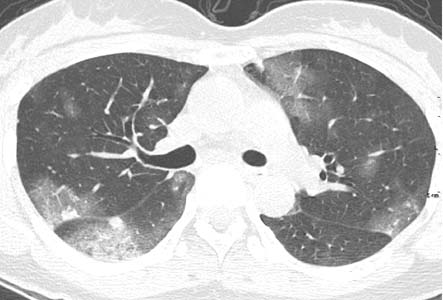

患者女性,43岁,肝癌tace治疗后出现胸闷不适.

请分析肺部改变的成因及可能的诊断.

动静脉瘘,栓塞剂经瘘口进入肝静脉--下腔静脉--右心房--右心室--肺动脉--沉积于肺内.

原发性肝癌进行栓塞治疗时,若肝动脉造影显示肿瘤侵犯肝静脉,且有明显的肝动静脉瘘,则使用碘油乳剂就不妥当,因为大量碘油可通过瘘道进入肺部,引起肺栓塞的并发症。

国内颜志平等报道:动物实验表明,碘化油进入肺部致死量约为0.5ml/ kg ,少量碘化油进入肺部可通过肺部吞噬细胞进行“消化”,故少量碘化油进入肺部后一般经过对症处理后,一般不会遗留明显并发症。